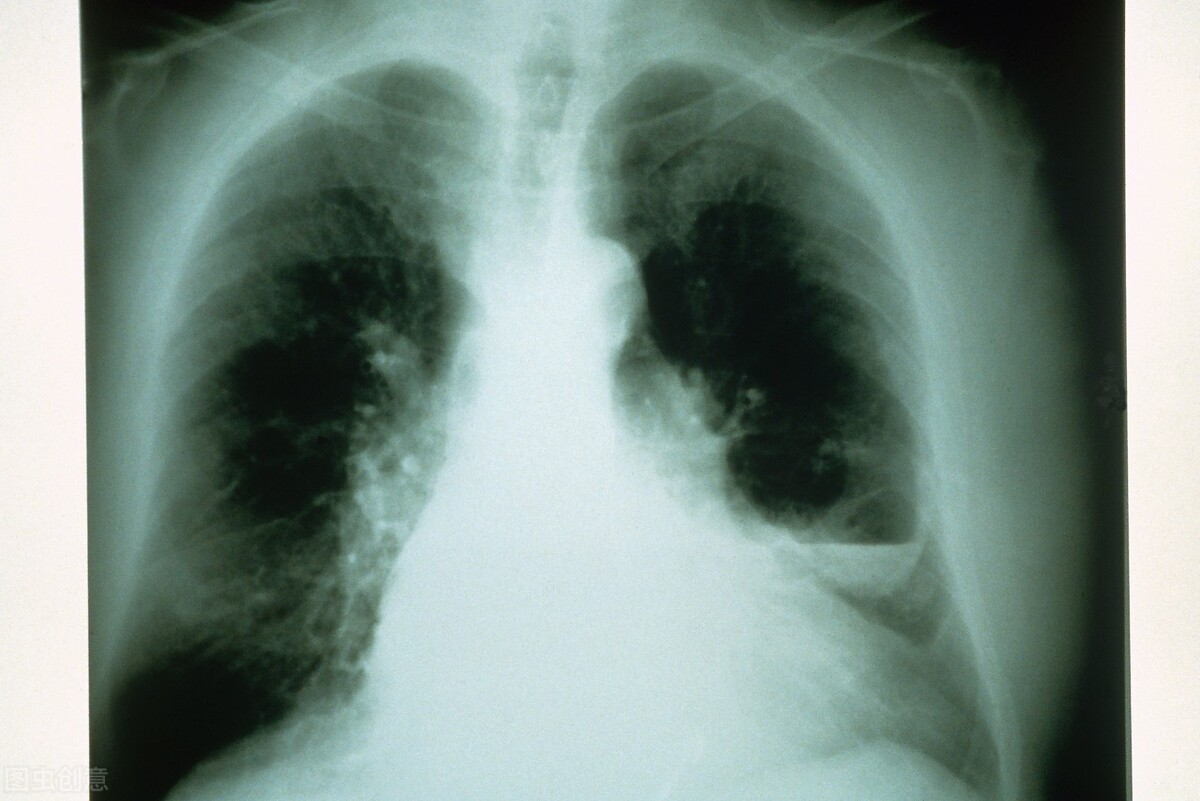

慢性支气管炎急性发作期的治疗手段包括两种,一种是对症治疗,另一种是对因治疗。

对症治疗,慢性支气管炎急性发作症状是咳嗽、咳痰、喘息等症状,治疗手段,比如止咳,用中医和西医止咳药物进行止咳治疗。化痰、祛痰治疗,治疗手段有人工排痰方法和哈气排痰方法,还可用药使黏痰松解,促进排出药物。

另外,喘息,对于急性发作期喘息较明显患者可进行雾化、扩张气道治疗,缓解支气管平滑肌痉挛和阻塞,同时给予吸氧,严重病人可给予呼吸机治疗。

分辨病人出现慢性支气管炎急性发作的原因,就是对因治疗,能诱发慢性支气管炎急性发作的原因主要是感染,比如病毒感染、细菌感染或烟雾和*草烟**刺激。

对因治疗,如果判断为病毒感染,要进行抗病毒治疗。如果是细菌感染,根据药敏试验或经验进行抗细菌治疗,抗生素治疗。如果是*草烟**刺激,要让病人戒烟。